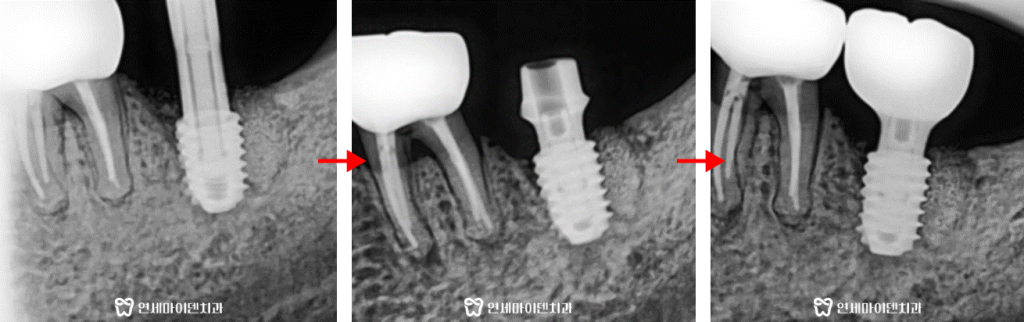

신경관이나 다른 구조물에 닿지 않도록 세밀하게 계획해야 합니다.여러번의 모의 시술 끝에 발치 즉시 임플란트 수술을 진행합니다.

발치 당일 임플란트를 식립함으로써

임플란트 기간을 단축하고 빠른 회복이 가능합니다.환자분께서도 임플란트 치료 기간을 1년 이상으로 생각하셨다가

발치 즉시 임플란트를 통해 단축된 치료 기간에 깜짝 놀라셨습니다.현재는 최종 보철 이후 정기검진을 오시면서

뼈가 잘 회복되는지, 다른 치아에 문제는 없는지 꾸준히 추적관찰 하고 계십니다.발치 즉시 임플란트는 환자의 뼈나 잇몸 상태에 따라